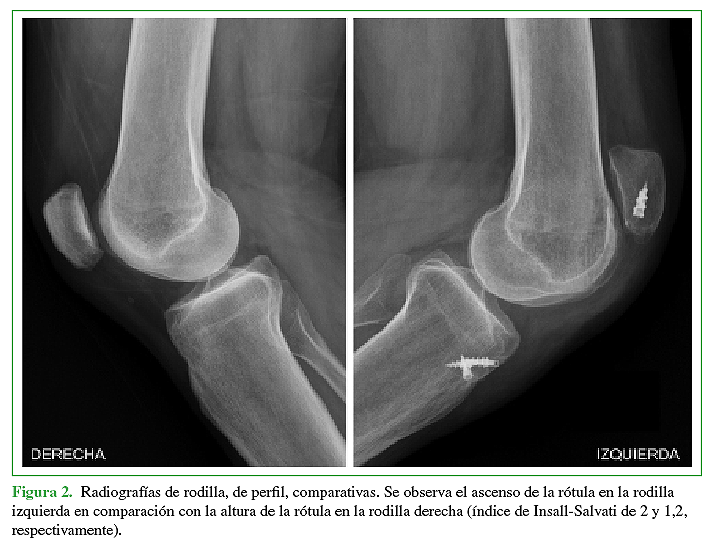

La rotura primaria del tendón rotuliano es una patología poco frecuente que afecta principalmente a adultos activos jóvenes. Aún menos frecuente, es la rotura crónica o recurrente del tendón rotuliano, y es esta última situación, la que presenta una importante dificultad técnica a la hora de realizar el debido tratamiento quirúrgico. El objetivo de este trabajo es la presentación de un caso donde se realizó la reconstrucción quirúrgica del aparato extensor mediante la utilización de aloinjerto luego de haber presentado tres cirugías fallidas para la reparación del tendón rotuliano tras sufrir una lesión traumática del mismo. Se describe tanto la técnica quirúrgica como también el protocolo de rehabilitación.Descargas